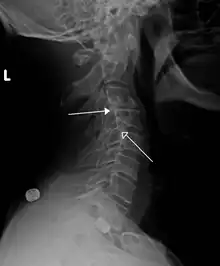

| Grade 1 retrolistheses of C3 on C4 and C4 on C5 | |

A retrolisthesis is a posterior displacement of one vertebral body with respect to the subjacent vertebra to a degree less than a luxation (dislocation). Retrolistheses are most easily diagnosed on lateral x-ray views of the spine. Views where care has been taken to expose for a true lateral view without any rotation offer the best diagnostic quality.

Retrolistheses are found most prominently in the cervical spine and lumbar region but can also be seen in the thoracic area.